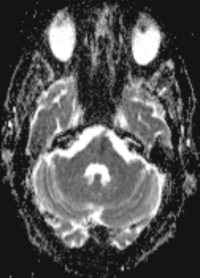

Series 001 — Frontal Lobe Mass (Likely Meningioma) Overview

Initial scan set with key anatomical landmarks and first-pass observations.